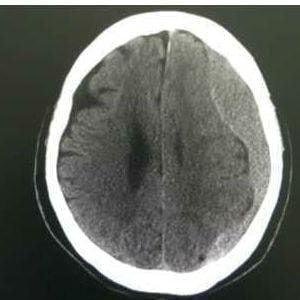

慢性硬膜下血腫

頭痛にはいわゆる慢性頭痛と命の危険を伴う頭痛があります。命の危険が伴う頭痛の原因はくも膜下出血、脳出血、慢性硬膜下出血などがあります。慢性型頭痛には緊張型頭痛、片頭痛、群発頭痛があり症状、治療法が異なります。